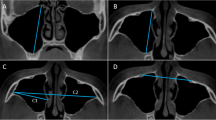

In this study, linear data of the maxillary sinus in the population of northwest China by using Cone-Beam Computed Tomography (CBCT) were collected and utilized to develop logistic, K-Nearest Neighbor (KNN), Support Vector Machine (SVM) and random forest (RF) models for sex estimation with R 4.3.1. CBCT images from 477 samples of Han population (75 males and 81 females, aged 5–17 years; 162 males and 159 females, aged 18–72) were used to establish and verify the model. Length (MSL), width (MSW), height (MSH) of both the left and right maxillary sinuses and distance of lateral wall between two maxillary sinuses (distance) were measured. 80% of the data were randomly picked as the training set and others were testing set. Besides, these samples were grouped by age bracket and fitted models as an attempt.